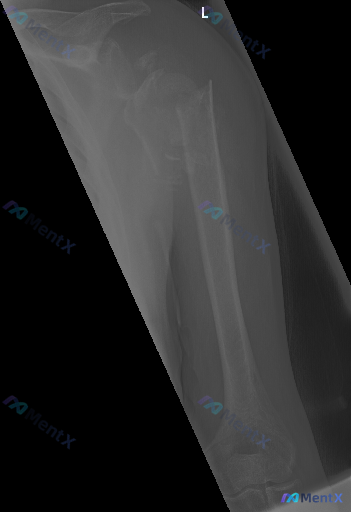

左上臂X线片:这组影像表现,核心异常该如何排序判断?

整理到一份影像资料:左上臂X光正位片,结合影像学描述如下:

骨骼情况:左侧肱骨近端可见骨折征象,累及外科颈及大结节区域,呈粉碎性表现;骨皮质连续性中断,多处碎裂分离;肱骨头与肱骨干间有显著移位、成角,断端可见分离及重叠;骨折部位骨小梁结构紊乱,见透亮骨折线。整体骨质密度尚可,未见明显骨质疏松或溶骨性/成骨性病变,无明显骨膜反应。

关节情况:肱骨头与肩胛盂对合关系异常,呈半脱位改变;影像显示范围内肘关节结构大致清晰,未见明显骨折或脱位征象。

软组织情况:左侧肩部及上臂近端软组织影增厚、密度增高,轮廓模糊。

无明显骨质增生或严重骨关节退行性改变征象。